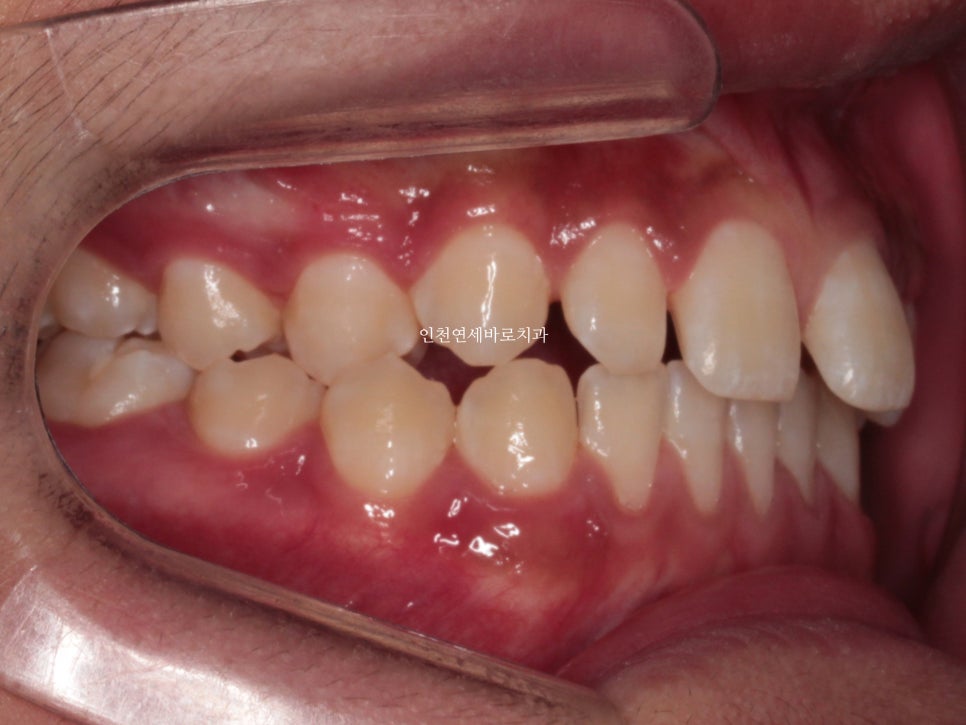

화살표쪽에 보이는 반대교합도 문제였습니다.

고무줄도 사용하여야 하며, 필요시 #미니스크류 도 식립해야 합니다.

문제가 되었던 오른쪽 어금니 교합도 좋게 마무리 하였습니다.